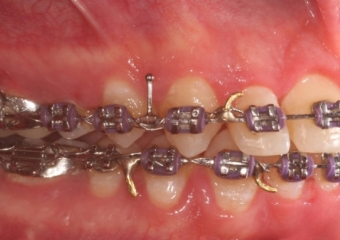

Mordida inicial